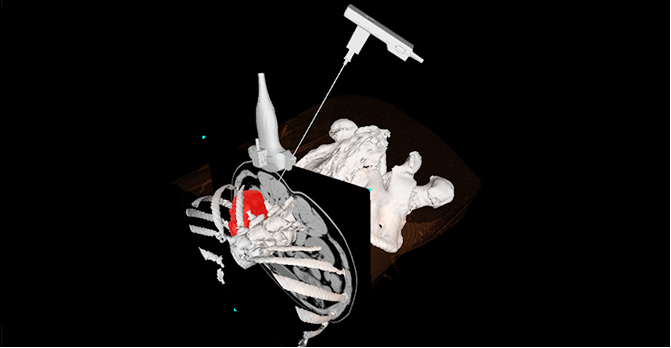

AI辅助针尖动态识别

精准引导建立手术通道